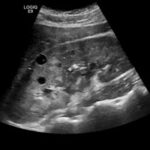

Ultrasound imaging (also called Sonography) is a method of obtaining diagnostic images from inside the human body through the use of high-frequency sound waves. Ultrasound is used as a diagnostic tool that can assist doctors in making recommendations for further treatment.

- Examining many of the body’s internal organs, including the liver, gallbladder, spleen, pancreas, kidneys, bladder, uterus, and ovaries.